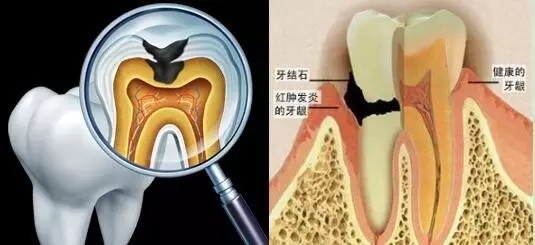

牙齿不齐不仅影响面型,也会因为不容易清洁口内残垢而易患龋齿、牙龈牙周炎症,甚至导致牙周病,造成牙骨萎缩牙齿脱落。

龋齿也就是蛀牙,是细菌性疾病可以继发牙髓炎和根尖周炎,甚至能引起牙槽骨和颌骨炎症。如不及时治疗,病变继续发展,形成龋洞,终至牙冠破坏消失,其发展的最终结果是牙齿丧失。所以大家在发现有蛀牙的时候要赶紧补牙,以免造成不必要的后果。

龋坏 牙周病

牙周病在早期不易察觉,主要的致病因素是牙齿表面的牙菌斑、软垢和牙结石。常见症状:牙龈炎症,出血,牙周袋形成,牙槽骨吸收,牙槽骨高度降低,牙齿松动,移位,咀嚼无力,所以遇到这种状况需要立即去齿科检查治疗。